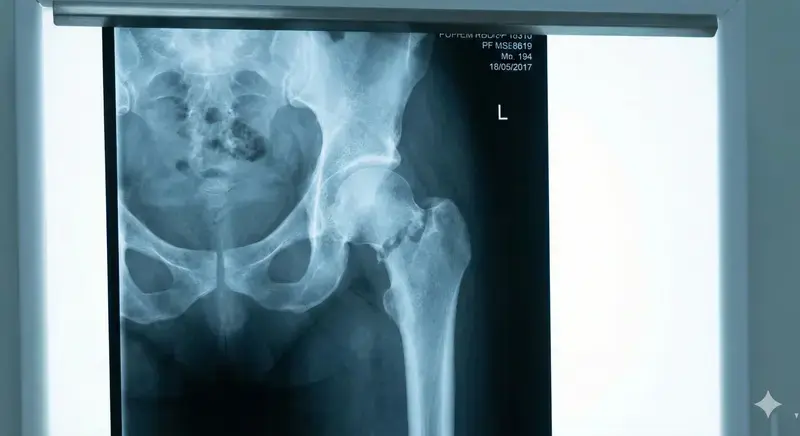

Quadril esmagado. Bacia partida. Artéria rompida. 45 dias para operar — ou cadeira de rodas para sempre.

Quadril esmagado contra o muro. Bacia partida em três lugares. Artéria femoral rompida — quase morreu de hemorragia. Impossível ficar em pé. Impossível andar. Dor constante, 24 horas por dia.

A cirurgia exige uma prótese de quadril importada.

O SUS faz a cirurgia, mas não cobre esse tipo de prótese. A fila para conseguir uma pelo sistema? 11 meses.